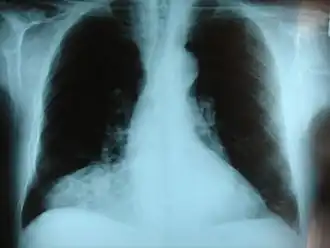

Frontale röntgenfoto van de borstkas. Er is een hernia van Morgagni te zien.

Er is een hernia van Morgagni te zien.